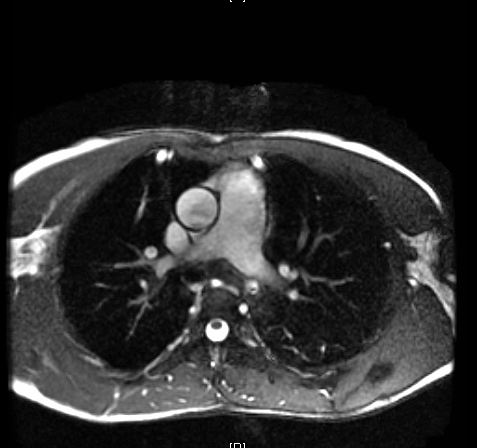

Case Presentation: An 18 year old Spanish speaking male from Honduras presented following a motor vehicle accident. Initial assessment in the ED included a CXR and bedside Echocardiogram which noted cardiomegaly and a reduced EF of 15%. Patient reports experiencing headaches, blurry vision, palpitations, and non-radiating left sided chest pressure intermittently over the last four years. He reported never having seen a physician and denied any family history of cardiac disease or sudden cardiac death. Physical was exam notable for systolic hypertension in the upper extremities, systolic ejection murmur left sternal border, diminished femoral pulses, and thin lower extremities. The patient reported no other significant past medical history. 24-hour urine fractionated metanephrines and catecholamines were within normal limits, HIV and T. Cruzi antibodies were negative. Transesophageal Echo and Cardiac MRI revealed a bicuspid aortic valve with fusion of the right and left coronary cusps, moderate-severe eccentric aortic regurgitation, severe global LV systolic dysfunction, and coarctation of the aorta. He subsequently underwent AV repair, Descending Aorto-bypass graft, and Coarctation of Aorta repair. Follow up Echo revealed elevated mean transaortic valve gradient in the presence of a bioprosthetic aortic valve and severely dilated left atrium.